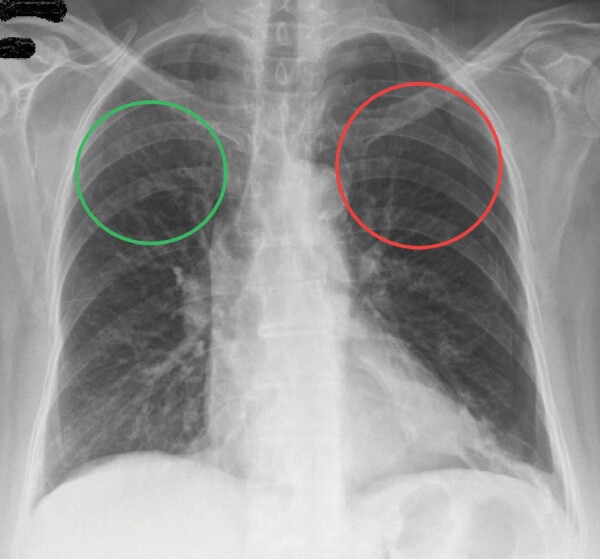

Birt-Hogg-Dubé syndrome: A case series highlighting pulmonary manifestations, rare renal involvement and role of familial diagnosis.